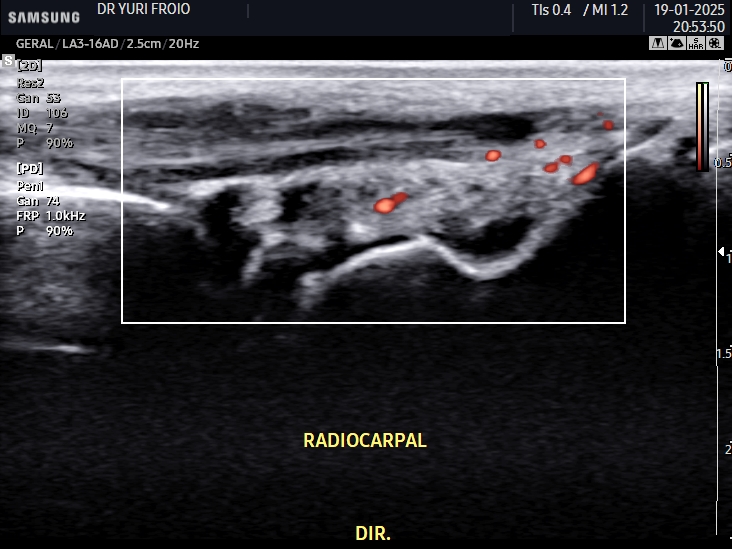

Ecografia Vascular com Doppler

A ecografia vascular com Doppler avalia o fluxo sanguíneo em artérias e veias identificando obstruções, varizes e tromboses. É um exame não invasivo, essencial para diagnóstico e acompanhamento de doenças vasculares. Proporciona informações detalhadas para uma abordagem clínica precisa.